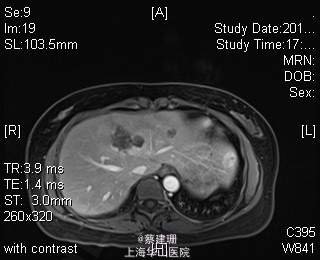

主诉:平滑肌肉瘤、肝转移癌术后,发现肝多发转移2月余。 现病史:患者3年前外院检查发现后腹膜肿瘤,外院行后腹膜肿瘤切除术后,术后病理为:平滑肌肉瘤,2013年12发现肝左叶转移癌,外院行肝左叶肿瘤切除术,术后病理为:梭行平滑肌肉瘤。2月余前患者复查发现肝脏多发转移,2015-4月肝脏MRI:肝脏多发转移。现患者无恶心、呕吐,无呕血、黑便,无皮肤巩膜黄染,无剧烈腹痛发作。现为进一步诊治收住入院。

查体:锁骨上淋巴结未扪及肿大;腹部平坦,可见陈旧性手术疤痕。未见肠型、胃型蠕动波,腹软,无压痛及反跳痛,无肌卫,肝脾肋下未及。Murphy’s 征(-),肝区叩击痛(-),肾区叩击痛(-);移动性浊音阴性。 辅查:2015-4月肝脏MRI:肝脏多发转移。

诊断 :1、多发肝转移癌 2、后腹膜平滑肌肉瘤术后 3、肝转移癌术后 处理:取右侧肋缘下切口,左侧延长,逐层切开进腹,探查腹腔:见上腹部粘连,仔细游离上腹部腹腔粘连,探查见无腹水,胃、肠、胰、脾及盆腔脏器未及异常,腹腔未见明显转移结节;肝脏无硬化。肝门淋巴结无肿大,门静脉主干无栓子。肿瘤多枚,最大两枚位于肝右叶VI段,肿瘤大小约7*6*5cm。V段肿瘤直径约5cm。左内叶肿瘤多枚,直径0.5-4cm,紧贴第一肝门。左外叶肿瘤多枚,直径1-3cm,肿块质韧,边界尚清,有包膜。术中诊断为转移性肝癌,决定行左半肝切除,肝右叶特殊肝段切除。